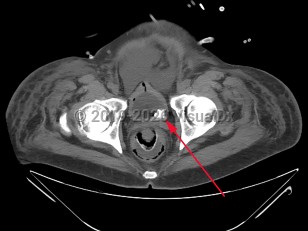

Urinary bladder calculus

The decreased incidence of bladder calculi is largely because the 2 conditions principally associated with bladder stones, urinary stasis (most commonly due to benign prostatic hyperplasia [BPH]) and urinary tract infections (UTIs), are now more easily and frequently treated. BPH, once only effectively treated with surgery, is now frequently effectively and more easily treated with a combination of alpha blockers, 5-alpha reductase inhibitors, or transurethral resection. Consequently, the number of men suffering from chronic urinary retention has significantly decreased. Urinary stasis in the setting of neurogenic bladder is also a common etiology of bladder stone formation.

When urine is chronically retained in the bladder, any nidus, such as a small fragment of a stone passed from the ureter, a bladder diverticulum, or a foreign body such as a ureteral stent or Foley catheter, can serve as a site for the precipitation and deposition of uric acid. In most retrospective studies of bladder stone composition, nearly all stones (as many as 80%) are entirely composed of uric acid, and most of the remainder contain a substantial portion of uric acid. Interestingly, neither gout or hyperuricemia appear to be contributory factors in the formation of bladder calculi. This is qualitatively different than nephrolithiasis, which in the United States is primarily due to calcium oxalate or calcium phosphate stones.

Bladder stones, particularly large and nonobstructive stones, do not frequently cause symptoms. Larger stones are thought to be less able to move significantly within the bladder and cause injury to the bladder wall and seem to be less prone to lodge in the bladder infundibulum / neck and cause acute obstruction. When patients do present with symptoms, they may be nonspecific and include suprapubic discomfort, hematuria, dysuria, urinary frequency, urinary hesitancy or poor urine stream, penile pain in male patients, or cloudy urine.